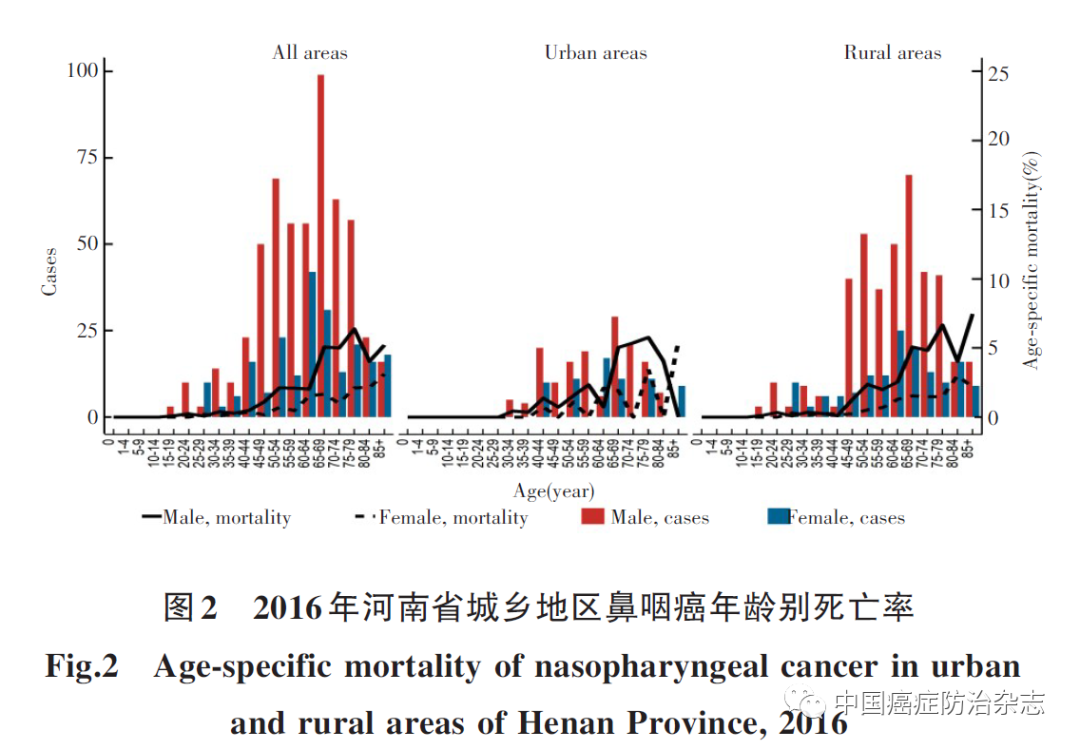

世界卫生组织国际癌症研究中心(IARC)的数据显示,2020年全球有13.3万鼻咽癌新发病例及8万死亡病例,其中我国有6.2万新发病例,3.4万死亡病例,疾病负担...